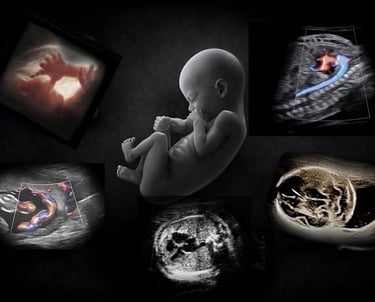

Free OB Ultrasound

The most powerful technology in medicine

is the person using it.